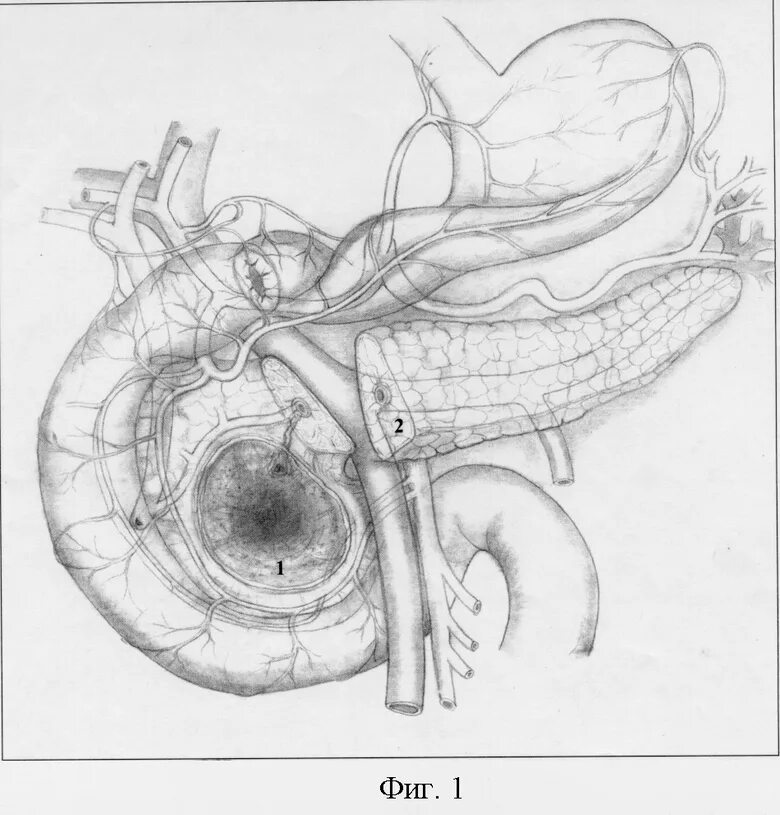

Диффузные изменения киста поджелудочной железы